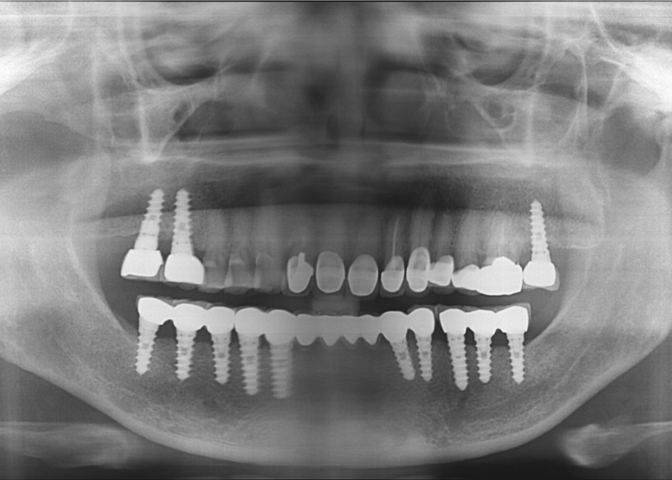

| surgery date | 2008.05.19 |

| gender | Female |

| age | 68 |

| surgery date | 2007.07.05 |

| gender | 성별 선택 |

| age | 73 |